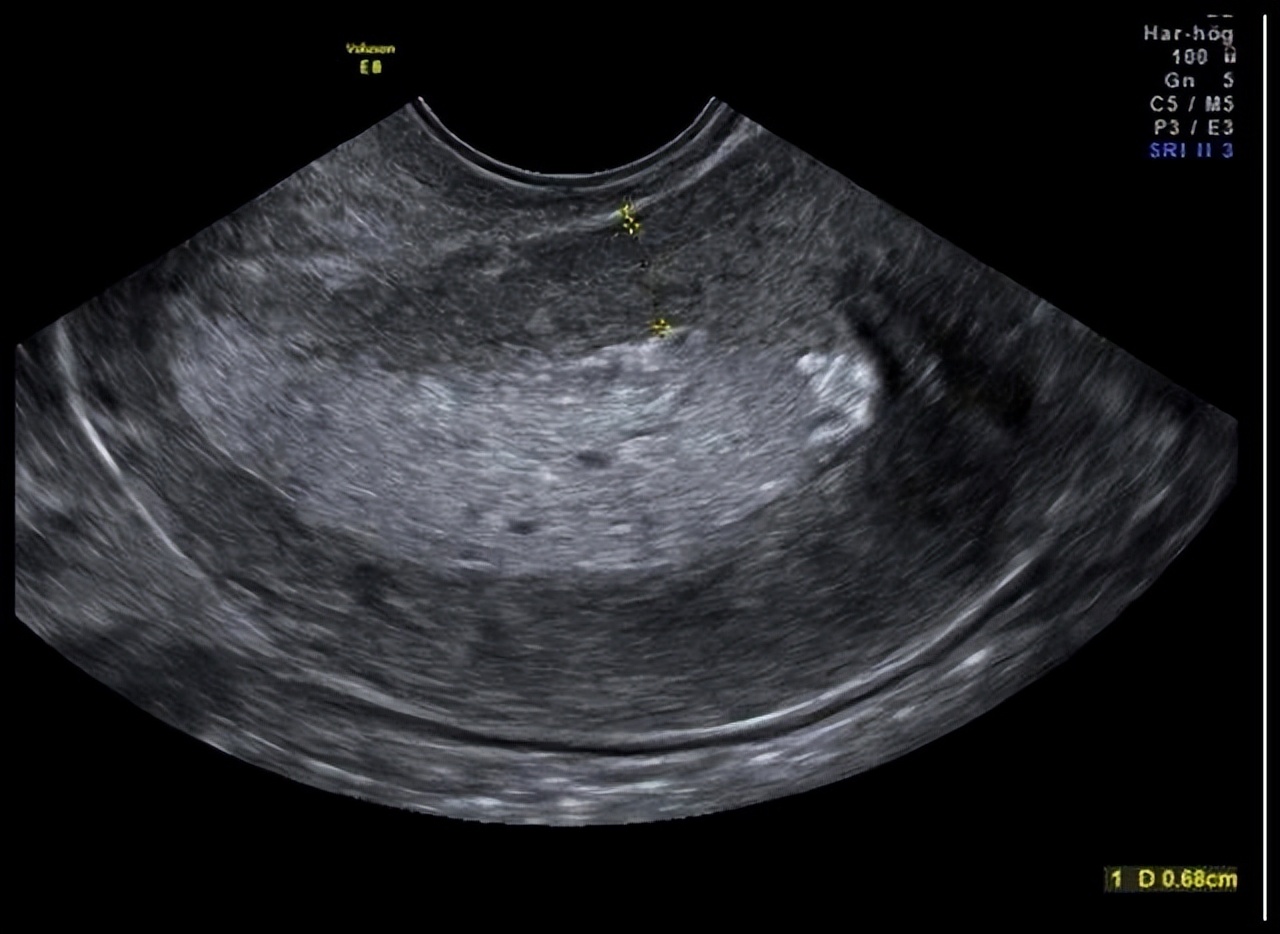

询问病史,小王以往月经规律,不存在痛经,怀孕过3次,生产过1次,身体健康,没有药物过敏史及手术史等。 再次做子宫、附件超声检查,子宫形态正常,肌层回声均匀,内膜厚0.5厘米,回声均质,双侧附件区未见明显异常,盆腔未见明显液暗区,CDFI未见明显异常血流信号。